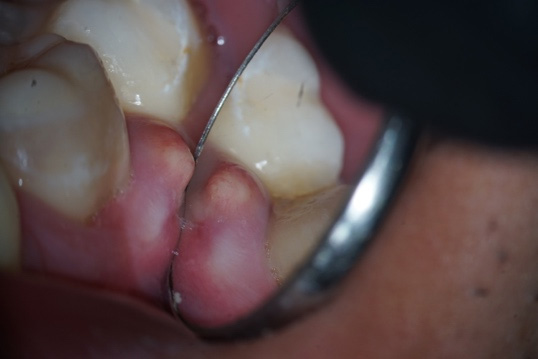

Cervical Radicular Perforation: Case Report

The use of MTA-based endodontic cements in root perforation treatment

Endodontic retreatment with root perforation using MTA repair cement and MTA based sealer